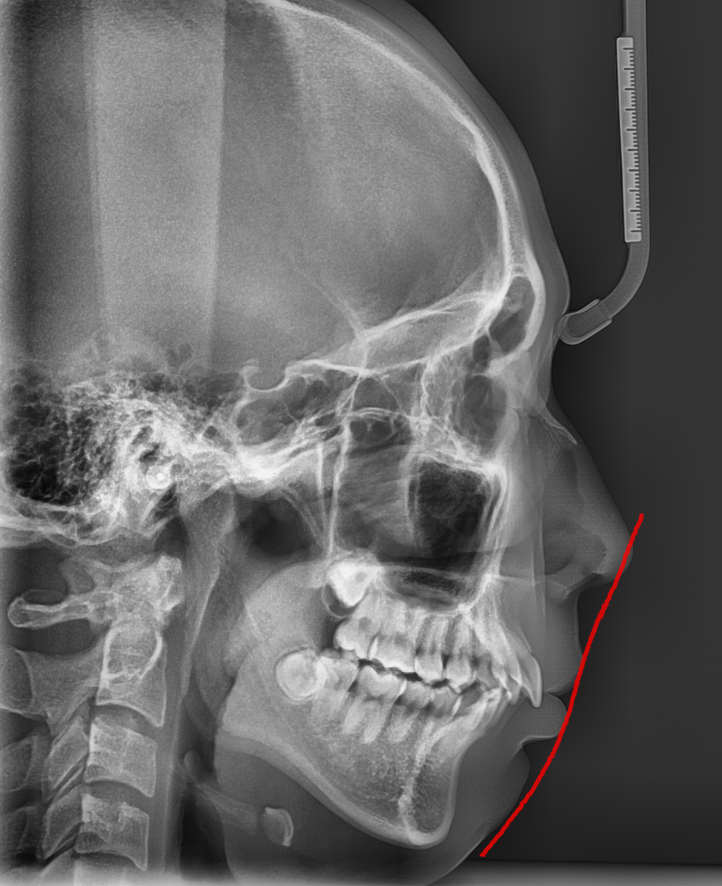

250228 환자분들은 옆 라인 개선을 1순위로 많이들 말씀해주시죠~

대신 입이 들어가면서 입매가 변화

심미적인 효과를 얻을 수 있는데요.